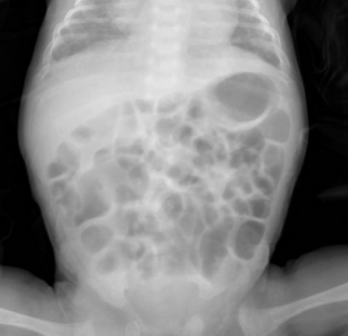

临床病例:患儿日龄1个月12天,女,孕1产1,在孕26周时因“胎盘早剥”剖宫产娩出,无胎膜早破,血性羊水,出生体重660g,双胎之先娩出者,生后Apgar评分1分钟为8分,5分钟、10分钟均为9分,以“超早产儿、超低出生体重儿、新生儿呼吸窘迫综合症、双胎儿”转入我科进一步治疗。患儿入院后予早产儿配方奶喂养。患儿奶量增加缓慢。表现为腹胀、肠鸣音弱、奶量增加困难、偶有吐奶、排粘液便。无肉眼血便。化验检测显示嗜酸性粒细胞增高,波动在20-25%之间。间断监测腹片显示肠管僵直、肠管充气不均匀(如下图所示)。未见肠壁积气和门静脉积气。患儿有过敏性疾病家族史。予更换为深度水解奶后患儿腹胀较前缓解,肠管充气均匀,无明显扩张。奶量增加顺利。嗜酸性粒细胞下降至5-8%。

更好奶粉后